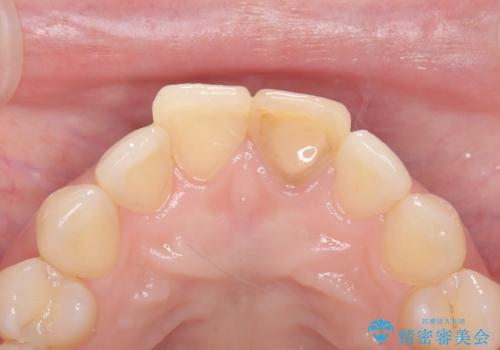

前歯の変色を改善し、本来の自然な美しさへ

- 以前の根管治療後に生じた左上1番の前歯の変色を気にされて来院されました。患者様のご希望を伺い、オールセラミッククラウンによる審美修復を提案。既根管治療歯であるため、土台の状態や周囲の歯の色調を詳細に分析し、患者様の顔貌に調和した自然で美しい口元を実現するための治療計画を立てました。

治療では、変色した歯を形成した後、精密なシリコン印象材で型取りを行いました。この型取りから、患者様の歯の色や形、透明感を忠実に再現したオーダーメイドのオールセラミッククラウンを作製。金属を一切使わないため、アレルギーの心配がなく、歯ぐきの変色も防ぎます。技工士と連携し、天然歯と見分けがつかないほどの自然な仕上がりを追求。機能性と審美性を兼ね備えた、理想的な前歯を取り戻していただけました。